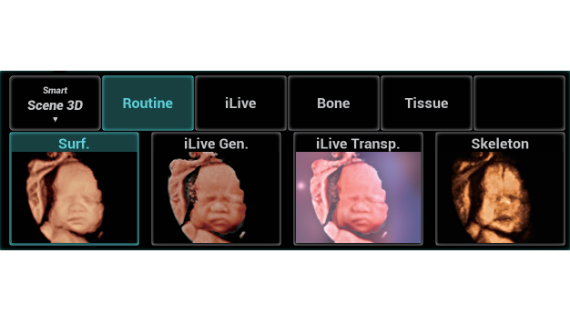

El sistema Nuewa I9, dise?ado exclusivamente para la atenciĂłn mĂ©dica neonatal y de mujeres, brinda una experiencia innovadora integral. Estas innovaciones se desarrollan sobre la base de un conocimiento profundo de situaciones clĂnicas complejas para proporcionar respuestas precisas y oportunas, una gran eficiencia y una experiencia de usuario extraordinaria.

La plataforma ZST+?es una innovaciĂłn extraordinaria que representa toda una evoluciĂłn en el ĂĄmbito de la ecografĂa. Transforma las mĂ©tricas ecogrĂĄficas de la formaciĂłn de haces convencional al procesamiento basado en datos de canal. Supera la limitaciĂłn tradicional de tener que equilibrar entre resoluciĂłn espacial, resoluciĂłn temporal y uniformidad del tejido, con lo que ofrece una calidad de imagen excepcional para soluciones de producciĂłn de imĂĄgenes infinitas con mejoras continuas.